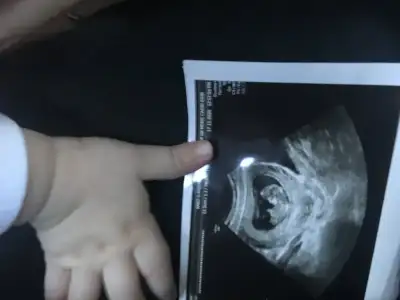

Emin olamadım başka USG varsa paylaşın sanki erkek gibi gibi ama emin değilimMerhaba 11+0 tahminde bulunur musunuz?

Birde bu var :)Emin olamadım başka USG varsa paylaşın sanki erkek gibi gibi ama emin değilim

Net değil olursa 12 13 haftalar paylasirsinBirde bu var :)